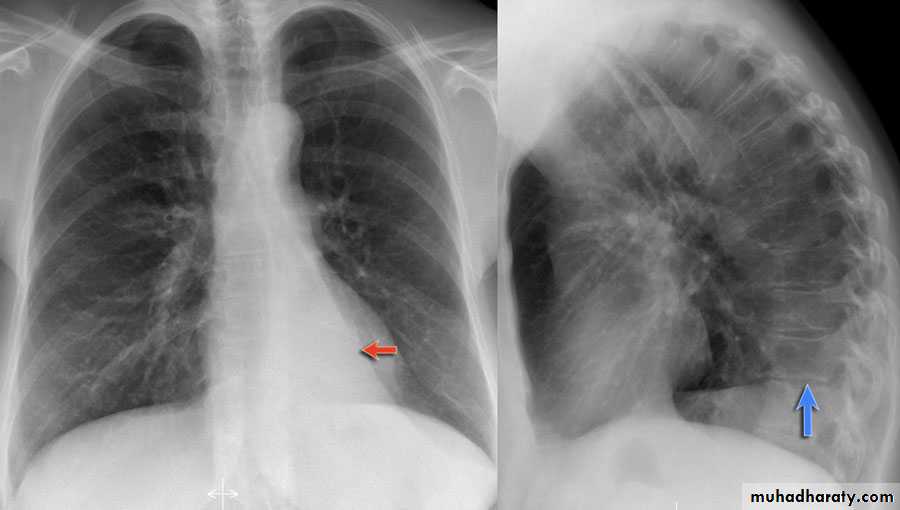

Area of hypertranslucensy (pneumothorax)

What is the difference?

(emphysematous bullae) (pneumothorax)